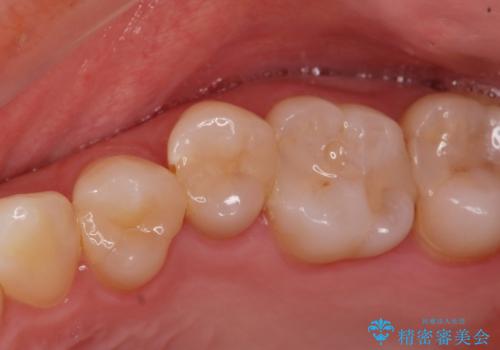

ZrCrの被せ物で治療を行いました。

また、一つ手前の歯に小さな虫歯があったため

e-maxインレーでの治療を行いました。

- ジルコニアクラウン・仮歯・e-maxインレー 19.8万円費用は治療当時の料金となります